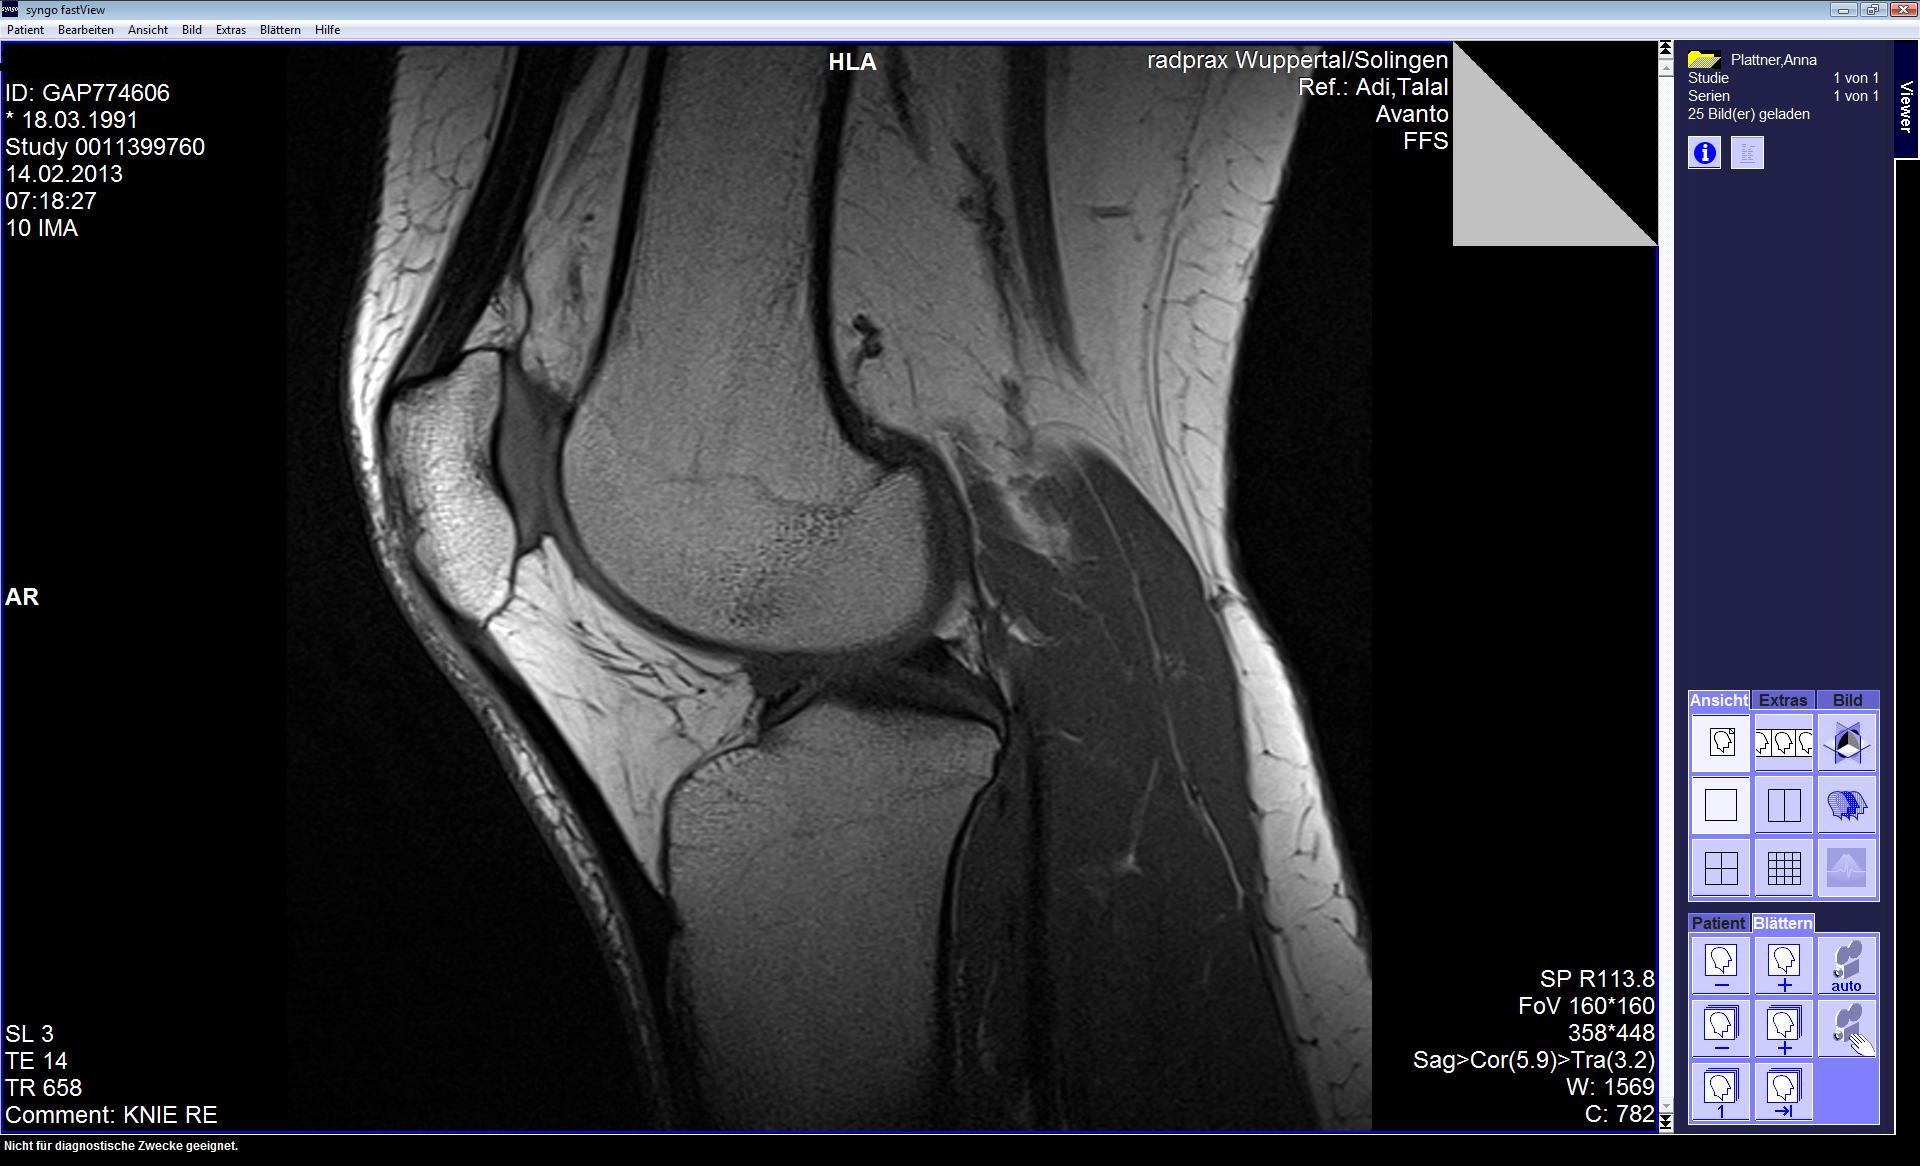

ich pausiere derzeit gezwungernermaßen zwangsweise (hab eine Verletzung am Menuskus am rechten Knie), möchte aber dann bald wieder anfangen zu laufen. Es juckt mir schon richtig in den Beinen und es fällt mir langsam schwer vernünftig zu sein und einfach sitzen zu bleiben. Aber ich denke mal sitzen bleiben ist besser als riskieren die Verletzung wieder zu verschlimmern.